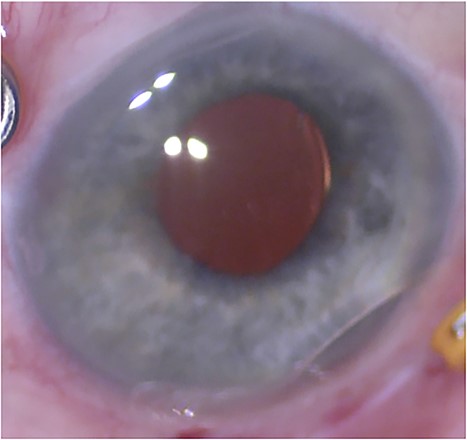

The patient underwent pars plana vitrectomy (PPV). The lens capsule was removed from the dislocated lens followed by same lens scleral fixation and 7–0 Vicryl sutures to the scleral tunnels (Fig. 1). Ophthalmic endoscopy confirmed final position of the lens haptic in the sulcus, and partial FAX was performed.

External photograph at the conclusion of initial scleral fixation. The IOL is well-positioned.